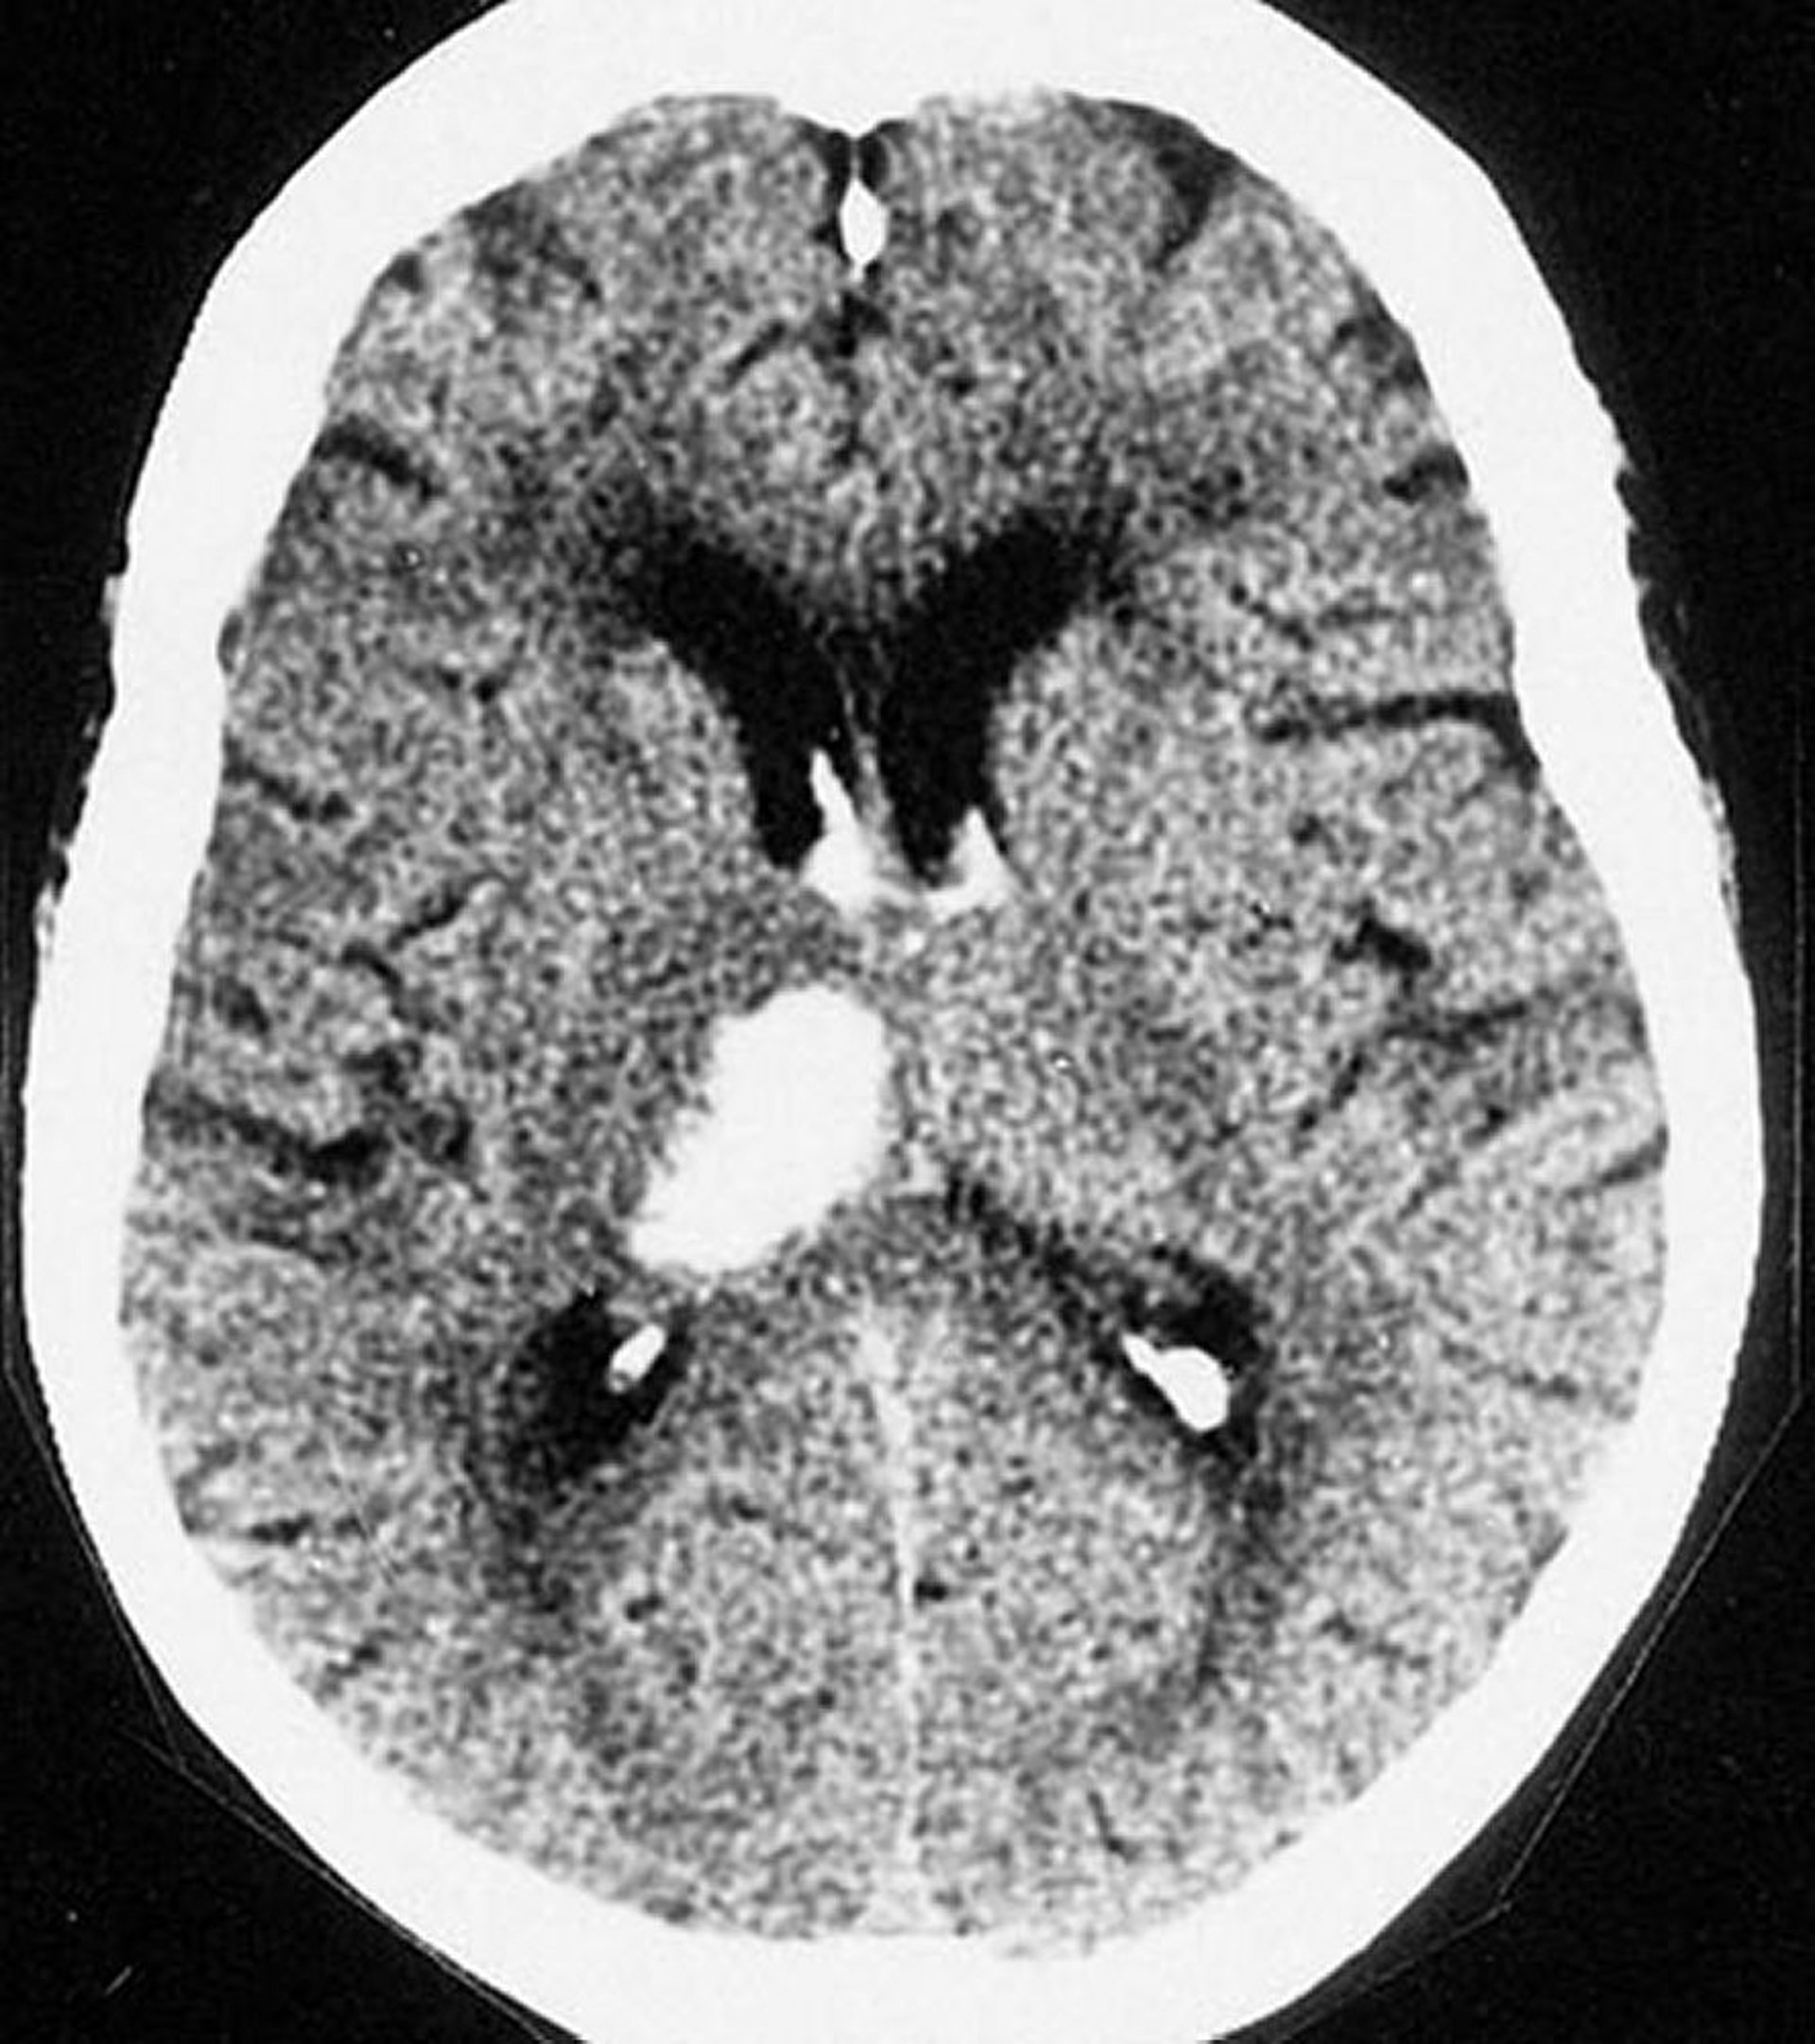

Hemorragia intracerebral talámica

Esta TC muestra una hemorragia en el tálamo. Las hemorragias intracerebrales suelen ocurrir en el tálamo y dentro de los ganglios basales.

By permission of the publisher. From Furie K, et al. In Atlas of Clinical Neurology. Edited by RN Rosenberg. Philadelphia, Current Medicine, 2002.